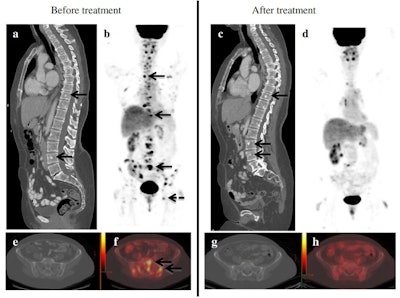

FDG-PET/CT can also provide clinical impact in treatment response and is "far superior to other methods when assessing response in patients with distant disease," Pinker-Domenig noted.

"Patients who have metastasis and receive treatment become non-FDG-avid and more sclerotic. With CT alone, we see new sclerotic lesions and it's impossible to know if it's progressive disease, or sclerotic bone metastasis, or treatment effect. This question is easily answered with an FDG-PET/CT scan, where the metastasis is no longer avid and sclerotic but clearly a treatment effect," she said.

In a study comparing FDG-PET/CT with contrast-enhanced CT for prediction of survival in patients with stage IV breast cancer, 43% of the RECIST non-responders were classified as responders with FDG-PET/CT.

"FDG-PET/CT provides significant clinical value accurately classifying responders as such," she said. "With FDG, we expand patient eligibility to other treatments."